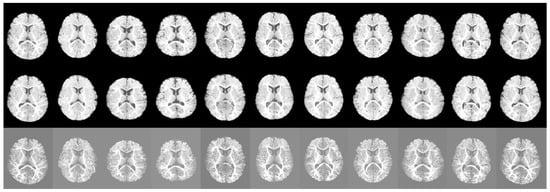

5.1. Segmentation Results